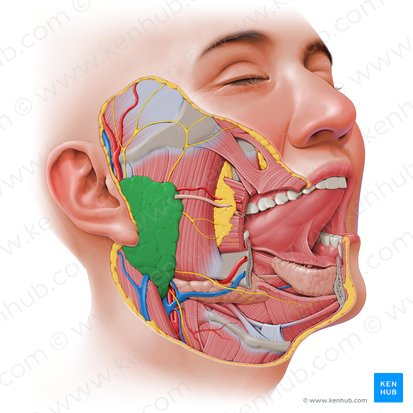

Parotid Gland

The largest of the major salivary glands, located superficially and somewhat posteriorly to the mandible (jawbone).

It produces saliva rich in enzymes (like amylase) which is secreted into the oral cavity to begin the digestion of carbohydrates.

Parotid Duct

The duct that carries saliva from the parotid gland into the oral cavity. It typically opens into the vestibule of the mouth (the space between the cheek and gums) near the upper second molar tooth.